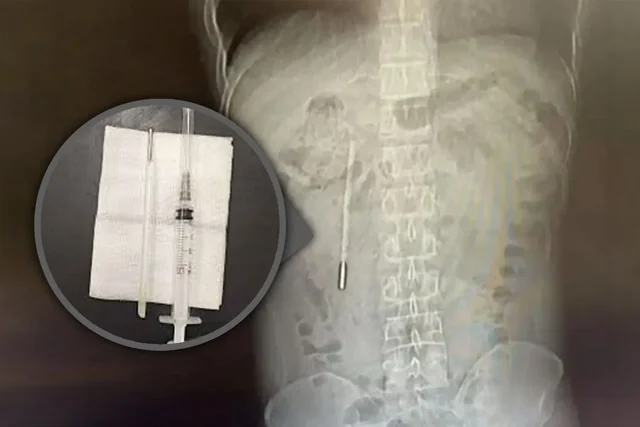

Хэвлийгээр өвдөх зовуурьтайгаар эмнэлэгт хандсан 32 настай Хятад эр шинжилгээнийхээ хариуг хараад шоконд оржээ. Шалтгаан нь түүний арван хоёр хуруу гэдэснээс 20 жилийн өмнө залгисан мөнгөн устай халууны шил олдсон байна.

Энэ тухай “South China Morning Post” хэвлэл мэдээллээ. Халууны шилний үзүүр гэдэсний хананд шууд тулсан байсан тул гэдэс цоорох, дотуур хүчтэй цус алдах маш өндөр эрсдэлтэй байсныг эмч нар онцолжээ.

Өвчтөн хожим тайлбарлахдаа, тэрээр 12 настай байхдаа санамсаргүй байдлаар халууны шил залгисан боловч эцэг эхдээ хэлэхээс айсандаа ийнхүү 20 жил нууж явсан гэжээ.